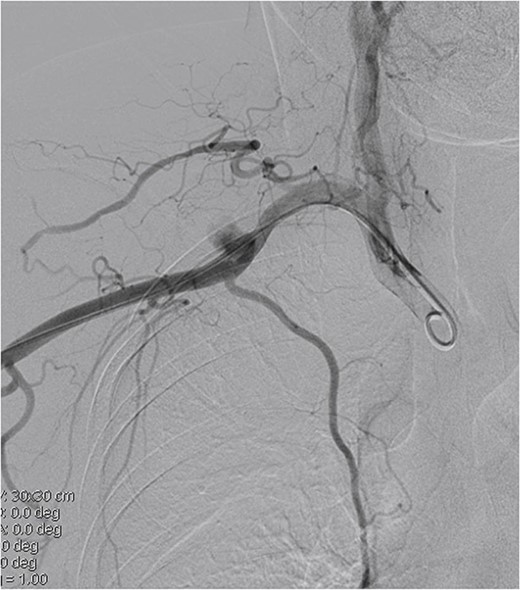

A 45-year-old female patient presented with a 20-day history of acute onset cooling, pallor, and paresthesia in the right upper limb along with supraclavicular discomfort on the right side. Notably, the patient’s medical history was devoid of significant conditions such as atrial fibrillation, hypertension, or coronary artery disease. Physical examination revealed a marked decrease in skin temperature, the absence of palpable radial and brachial pulses, and pallor in the affected extremity, with no detectable neurological deficits. Vascular ultrasonography revealed arterial thrombosis extending from the subclavian artery to the distal brachial, radial, and ulnar arteries. Computed tomographic angiography further characterized these findings, identifying filling defects in the right axillosubclavian vasculature indicative of a substantial clot burden. Intraprocedural digital subtraction angiography (DSA), conducted to facilitate endovascular thrombectomy, revealed a 12 × 12 mm pseudoaneurysm originating from the axillary artery (Fig. 1). The definitive treatment involved the deployment of an 8 × 60 mm (Fluency, Bard, USA) covered stent graft across the lesion in the vessel, followed by Fogarty balloon thrombectomy to re-establish distal perfusion (Fig. 2). Postoperatively, the patient received aspirin and short-term anticoagulation. Follow-up at 6 months, including clinical and ultrasonographic evaluations, confirmed symptom improvement, pulse restoration, and absence of ischemic or stent-related complications.

Covered stent placement isolates the pseudoaneurysm rupture, and further thrombectomy treatment is planned.